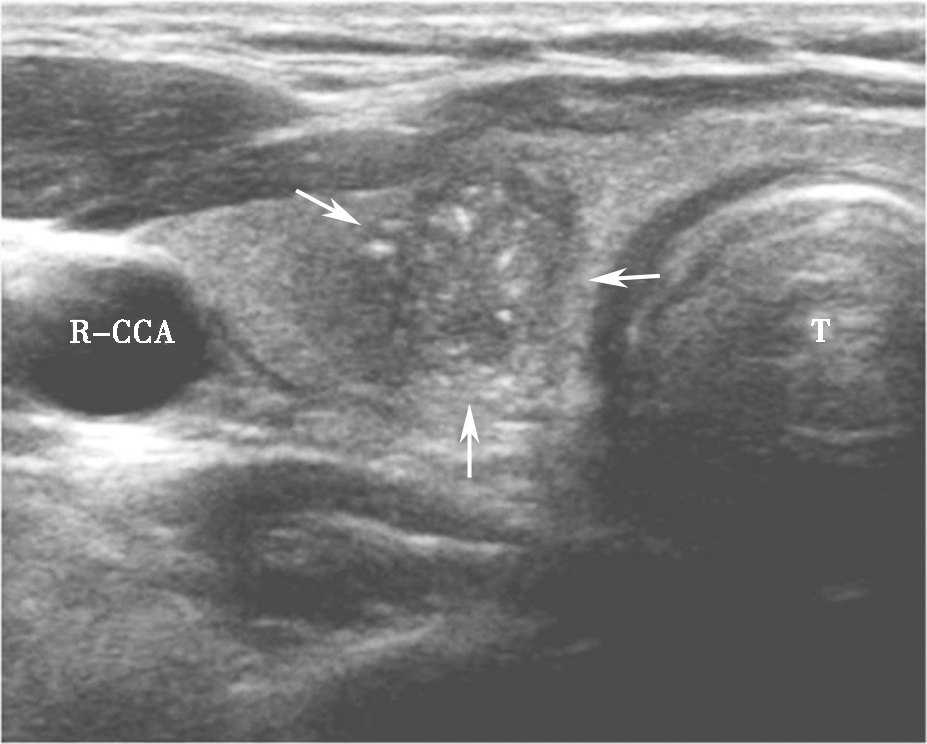

亚急性甲状腺炎超声表现为腺体内片状低回声,边界模糊,内可有散在的稍强点状回声,探头挤压时有压痛(图5)。低回声以外腺体彩色多普勒血流信号基本正常,低回声内部血流信号轻度增加或无明显增加,周边无明显血管绕行,部分低回声内部可显示正常甲状腺血管穿行。患者可伴有颈淋巴结增大。

图5颈部正中偏右侧横切面:甲状腺右叶饱满,可见片状低回声,边界模糊(箭头所示)R-CCA:右侧颈总动脉,T:气管